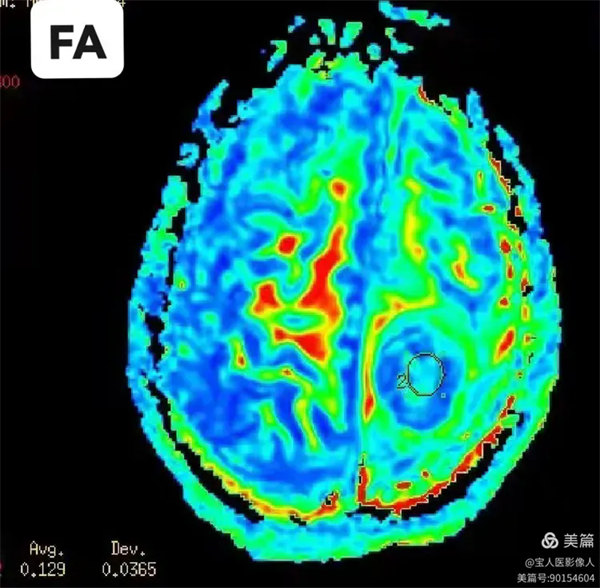

圖4:部分各向異性指數(FA)

病灶局部的各向異性指數值。(圖左下角顯示測量數值)